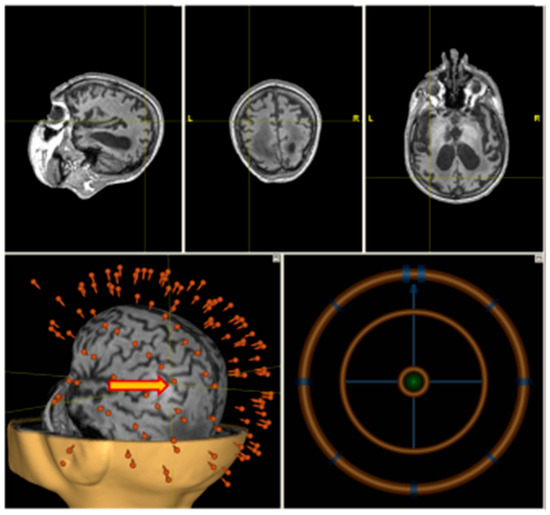

2.2. Structural MRI

2.3. rTMS